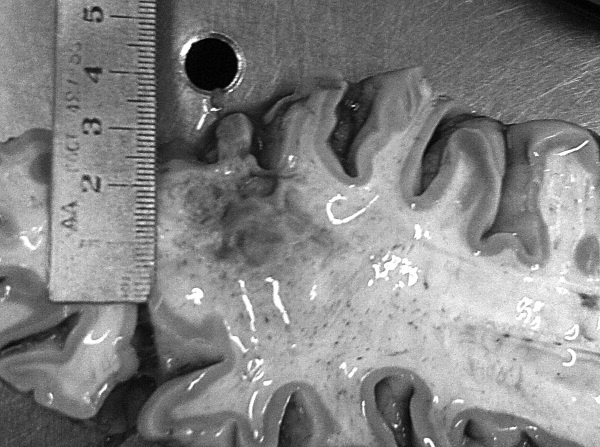

В посмертном эпикризе указан Основной диагноз: последствия ОНМК от 2008 года. ИБС. СН 2. ПИКС. Фоновое: СД 2-го типа, сопутствующее: хронический пиелонефрит. Осложнения: внебольничная пневмония. На секции: ![]() Рис. 31. Последствия перенесенного ОНМК ![]() Рис. 32. Атеросклероз церебральных артерий ![]() Рис. 33. Постинфарктный кардиосклероз ![]() Рис. 34. Гипертрофия миокарда левого желудочка ![]() Рис. 35. Признаки ХСН: мускатный фиброз печени ![]() Рис. 36. Пневмония ![]() Рис. 37. Признаки хронического пиелонефрита Анализируя данный клинический пример, необходимо отметить следующее. 1. Социальный статус. Социальный статус, за исключением указания на участие в ВОВ, не обозначен. 2. Наблюдение на дому. Полное несоблюдение регламента наблюдения ДИП. Клинический диагноз. Записи в амбулаторной карте нет. При этом диагноз должен быть следующим. Основной: последствия ОНМК от 2008 года. ИБС. Постинфарктный кардиосклероз. Фоновое: гипертоническая болезнь 3-й ст., 3 ст. риск 4. СД 2-го типа. Осложнения: длительная иммобилизация. Внебольничная пневмония. НК 2. Хронический пиелонефрит. Анемия. 3. Обоснованность назначения лекарственных препаратов. Терапия СД проводилась вне соответствия с клиническими рекомендациями, контроль за уровнем гликемии не осуществлялся, лечение анемии отсутствовало, вместе с тем при отсутствии подтвержденных данных за пиелонефрит были назначены антибиотики. Таким образом, наряду с указанными замечаниями врач не оценил тяжесть состояния, что не позволило решить вопрос о показанной госпитализации. Приложение № 6 – алгоритм лечения анемии. Приложение № 7 – самоконтроль уровня глюкозы. Пациентка Ф., 84 года. Умерла в январе 2011 года. Иммобилизирована с марта 2010 года в связи с закрытым переломом лонной и седалищной костей. В карте ежемесячные осмотры терапевта в связи с активами СМП. Причина вызовов: гипертонические кризы и болевой синдром. За год до смерти проведены доступные на дому анализы. В плановом порядке в апреле 2010 году проходила стационарное лечение в терапевтическом отделении. Диагноз при выписке: дисциркуляторная энцефалопатия 2-й ст. ГБ. ИБС. СН 3. ПИКС от 2001 года. Железодефицитная анемия. Закрытый перелом лонной и седалищной костей справа. Амбулаторно после стационара принимала энап Н и винпоцетин. В посмертном эпикризе указан Основной диагноз: 1) дисциркуляторная энцефалопатия 2-й ст. и ИБС. СН 3. ПИКС от 2001 г. НК 2А. Фоновое: ГБ. Сопутствующее: хроническая железодефицитная анемия. Закрытый перелом лонной и седалищной костей от 11.03.2010. ![]() Рис. 38. Повторный инфаркт головного мозга ![]() Рис. 39. Постинфарктный кардиосклероз ![]() Рис. 40. Атеросклероз коронарных артерий ![]() Рис. 41. Проявления НК: мускатный фиброз печени ![]() Рис. 42. Острые эрозии желудка ![]() Рис. 43. Атеросклероз аорты Замечания к ведению больного следующие: 1. Социальный статус. Информации нет. 2. Наблюдение на дому. Посещение терапевта осуществлялось только в связи с активами СМП. 3. Клинический диагноз. Нет правильной формулировки диагноза. При этом правильный диагноз был бы следующим. Основной диагноз: 1) Повторный инфаркт головного мозга. 2) ИБС. Постинфарктный кардиосклероз от 2001 года. Фоновое: гипертоническая болезнь 3 ст., 3 ст. Осложнения: закрытый перелом лонной и седалищной костей от 11.03.2010. Длительная иммобилизация. НК 2. Острые эрозии. Хроническая железодефицитная анемия. Сопутствующие: атеросклероз аорты. 4. Обоснованность назначения лекарственных препаратов: лекарственная монотерапия ГБ эналаприлом неэффективна, что повлекло за собой неоднократные гипертонические кризы и вызовы СМП, нет лечения проявлений ПИКС и анемии. Таким образом, не было оценки тяжести состояния, наличия тяжелой степени АГ у больной с перенесенным ОНМК и инфаркта миокарда, кризовым течением и признаками СН, что требовало госпитализации пациента. Приложение № 8 – ведение больного, перенесшего инфаркт миокарда. Пациентка Б., 95 лет. Иммобилизирована. Карта малоинформативна. Осмотры терапевта 1–2 раза в год, лист впервые выявленных диагнозов не ведется. Анализы отсутствуют. Известно, что наблюдалась с диагнозом ИБС, ЦВБ. Хронический бронхит. ОНМК с левосторонним гемипарезом и перелом шейки бедра без указания давности. В карте имеются указания на пролежни. За последние 2 года до смерти терапевтом были назначены: пирацетам, предуктал, мексидол, проведен курс ЛФК на дому. Посмертный эпикриз отсутствует. На секции: ![]() Рис. 44. Последствия перенесенного инфаркта головного мозга ![]() Рис. 45. Постинфарктный кардиосклероз |